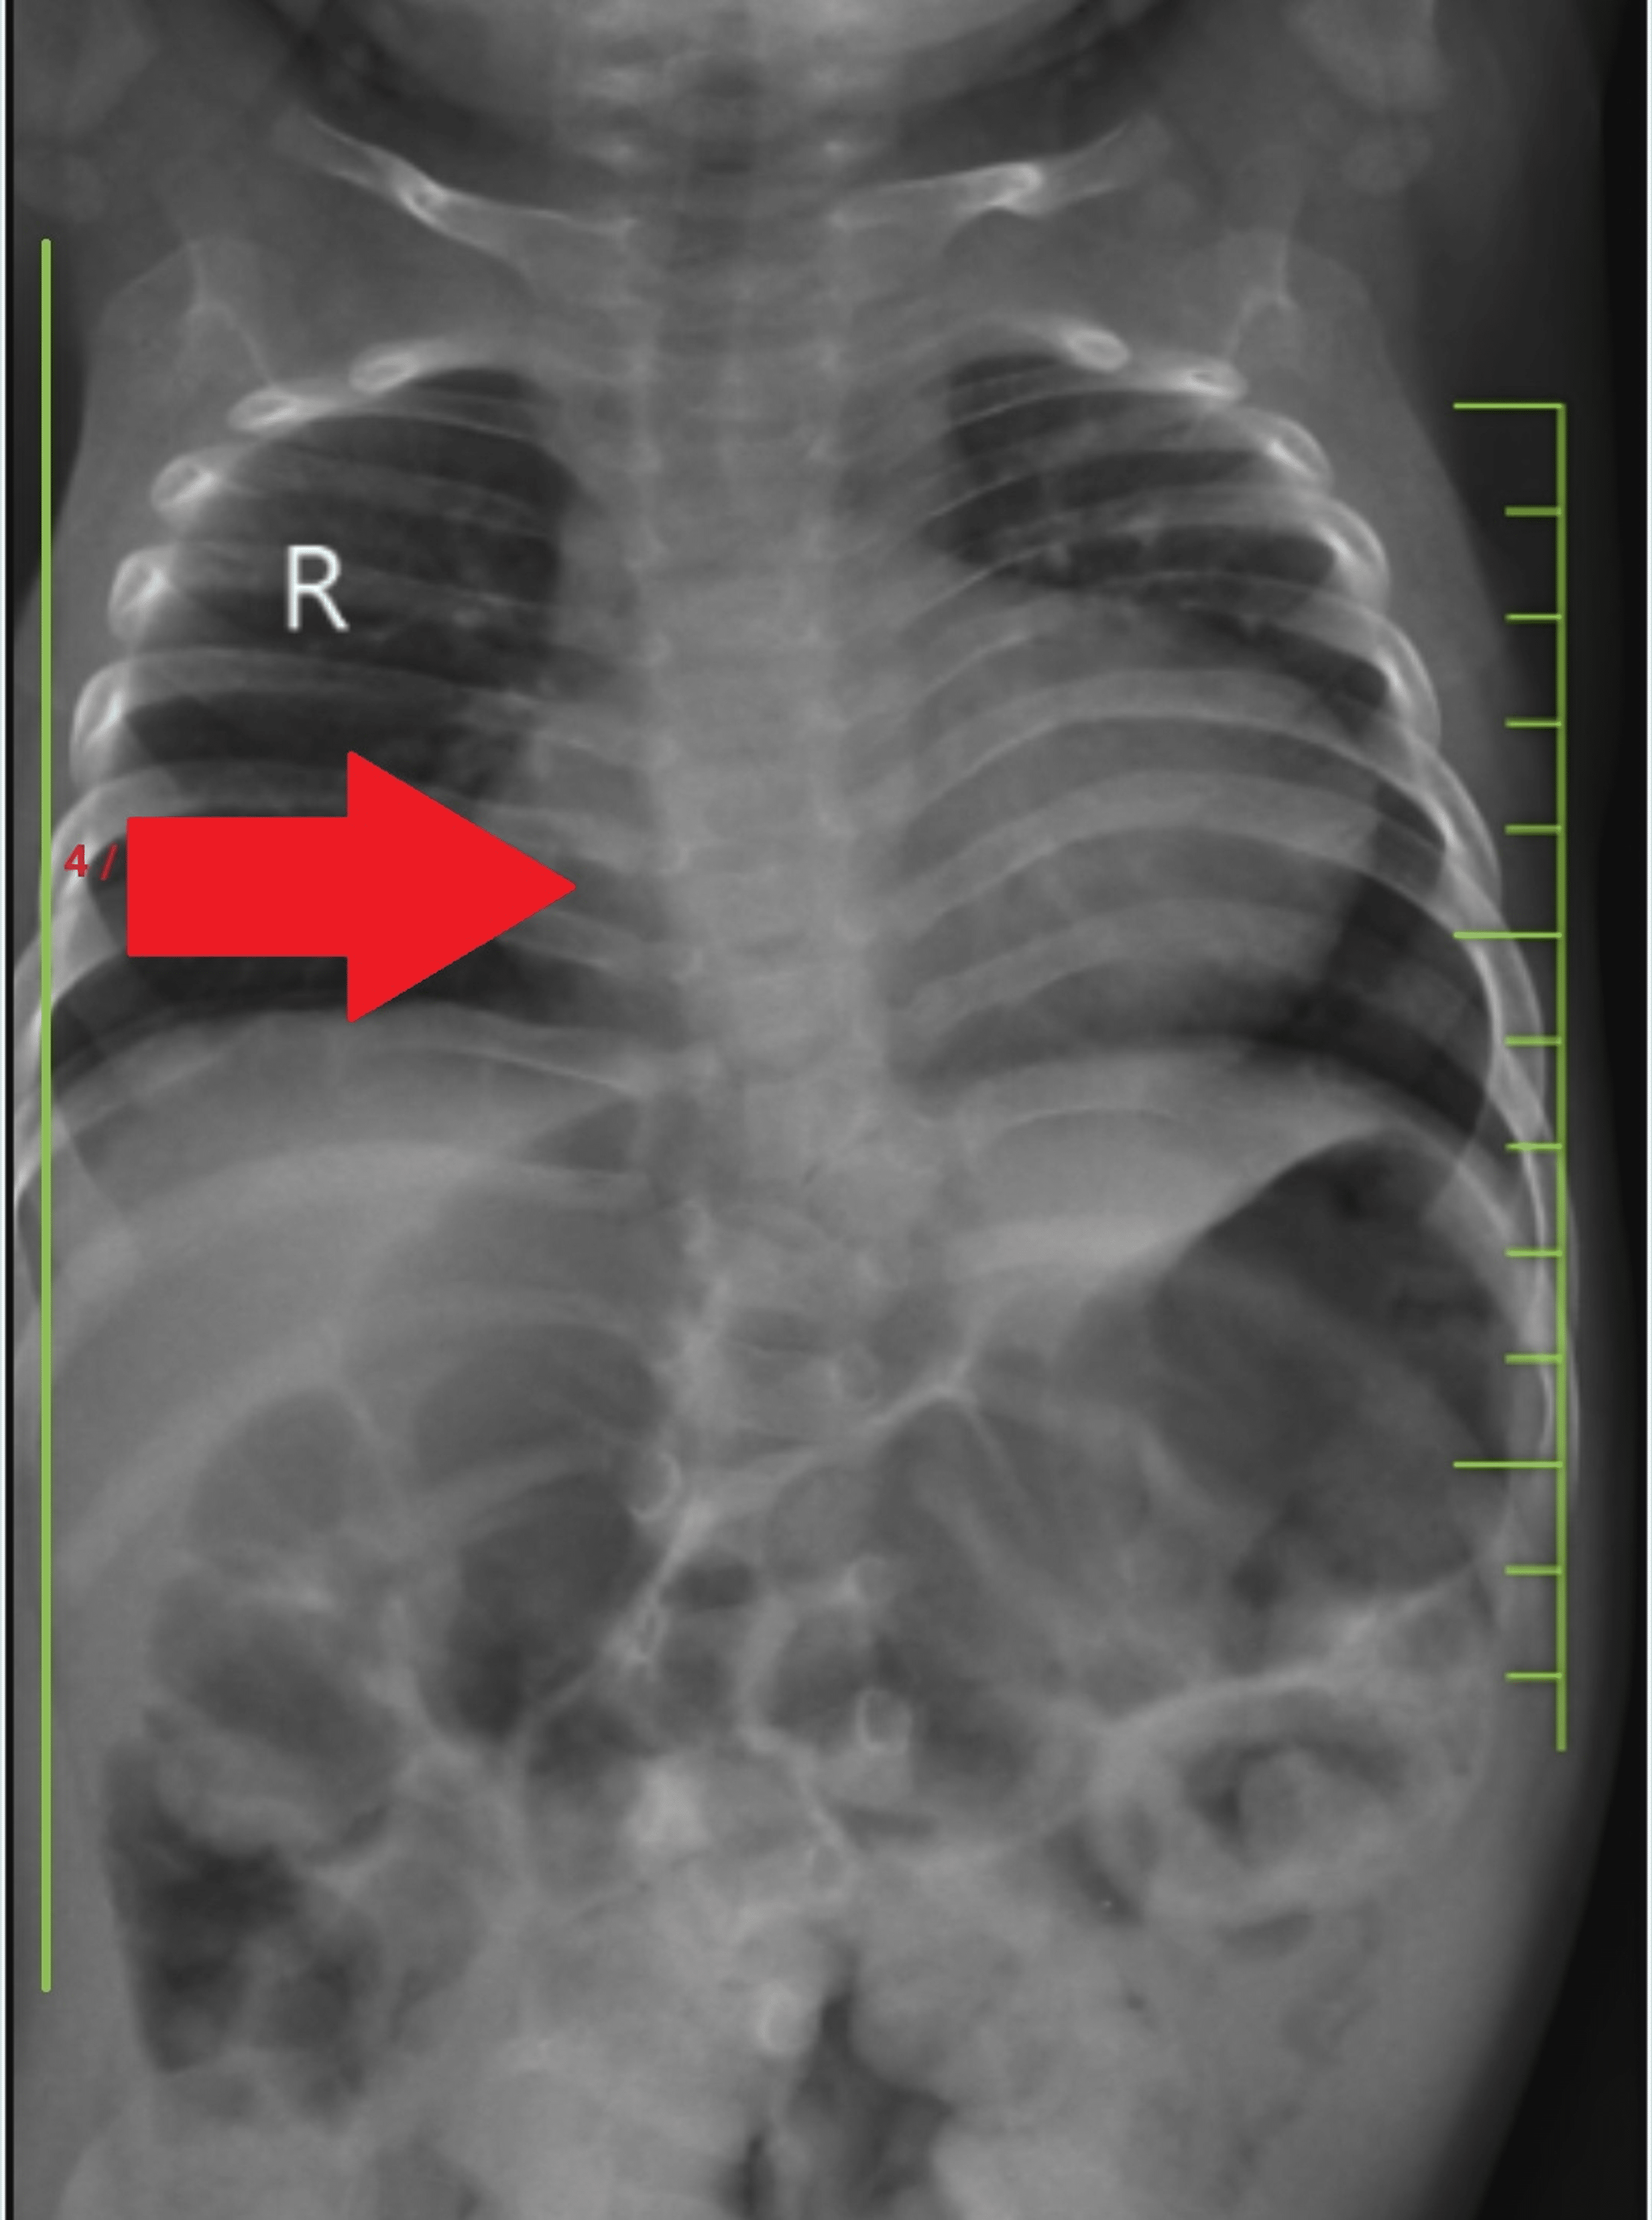

Bat's wing or butterfly pulmonary opacities refer to a pattern of

Pulmonary Edema X Ray Butterfly Pattern Butterfly Chest X Ray Notice the displacement of the. bat wing opacities, also known as butterfly opacities, refer to a pattern of bilateral perihilar lung shadowing. the “reversed pulmonary edema pattern” represents virtually a photographic negative of the “bat’s wing” or “butterfly” pattern and is characterized by homogeneous consolidations in the lung periphery running more or less parallel to the lateral chest. Butterfly Chest X Ray.

Chest Xray at admission shows " butterfly " pattern, characterized by Butterfly Chest X Ray Notice the displacement of the. bat wing opacities, also known as butterfly opacities, refer to a pattern of bilateral perihilar lung shadowing. the “reversed pulmonary edema pattern” represents virtually a photographic negative of the “bat’s wing” or “butterfly” pattern and is characterized by homogeneous consolidations in the lung periphery running more or less parallel to the lateral chest. Butterfly Chest X Ray.

Bat's wing or butterfly pulmonary opacities refer to a pattern of Butterfly Chest X Ray Notice the displacement of the. the “reversed pulmonary edema pattern” represents virtually a photographic negative of the “bat’s wing” or “butterfly” pattern and is characterized by homogeneous consolidations in the lung periphery running more or less parallel to the lateral chest wall. bat wing opacities, also known as butterfly opacities, refer to a pattern of bilateral perihilar lung. Butterfly Chest X Ray.